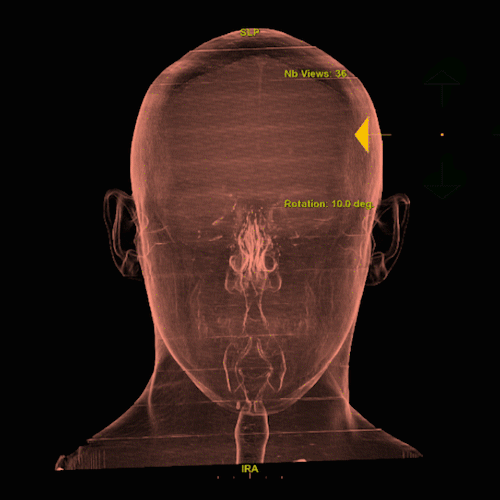

Our Facial Bones Service specializes in the analysis of facial trauma using 3D imaging derived from CT scans. This method involves volume rendering (VR) and segmentation techniques to map the skull base and facial bones, transforming traditional 2D CT images into 3D models. These models provide visualizations of the facial structure, highlighting fractures, dislocations, and other trauma-related anomalies.

This 3D imaging process allows healthcare professionals to assess the extent of facial injuries precisely. It is particularly beneficial for identifying fractures, evaluating the placement of surgical hardware, detecting abscesses, and diagnosing bony metastasis. By providing these precise visual tools, our service supports medical professionals in making informed decisions and optimizing treatment strategies for patients with facial trauma.